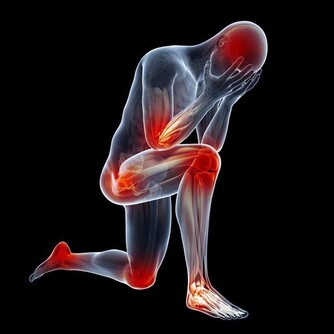

治療風濕:生薑具有特殊的驅寒祛風的功效,風濕患者每天晚上持續泡腳半小時,能夠有效地減輕病症。用木桶泡腳,泡過小腿,能夠緩解風濕關節炎。